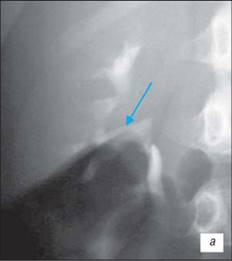

Висхідна цистографія

На даній рентгенограмі спостерігаємо активно-пасивний міхурово-сечовий рефлюкс зліва 4 ступені. Виражена дилатація чашечко-мисочкової системи, деформація чашок.

а – у фазі максимального наповнення сечового міхура, пасивний рефлекс;б – у фазі сечовипускання, активний рефлекс.